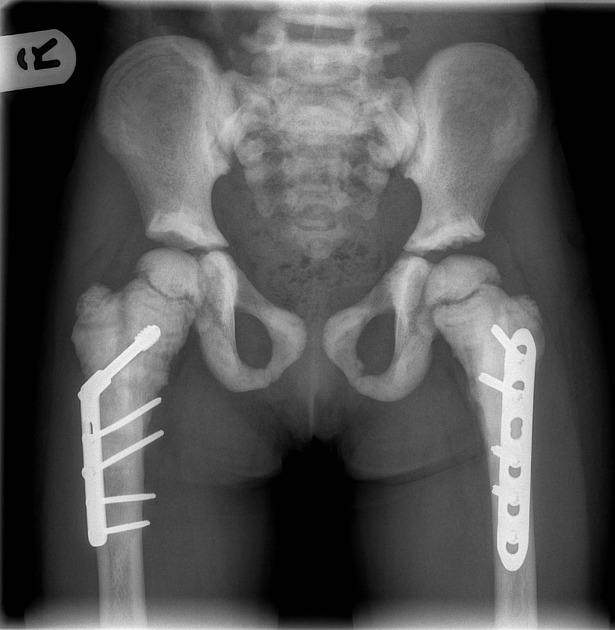

Obrazowanie stanowi podstawowy element diagnostyki osteopetrozy. Badanie RTG jest wystarczające do wstępnego rozpoznania, umożliwiając identyfikację typowych zmian, takich jak:

- uogólniona osteoskleroza (marble bone);

- deformacja kolby Erlenmeyera w przynasadach kości długich.

Tomografia komputerowa umożliwia ocenę stopnia sklerotyzacji, deformacji czaszki i kanałów nerwowych oraz wykrywanie złamań patologicznych. Rezonans magnetyczny pozwala ocenić stopień zajęcia szpiku i ewentualne neuropatie nerwów czaszkowych, w tym ucisk nerwów wzrokowych i słuchowych.